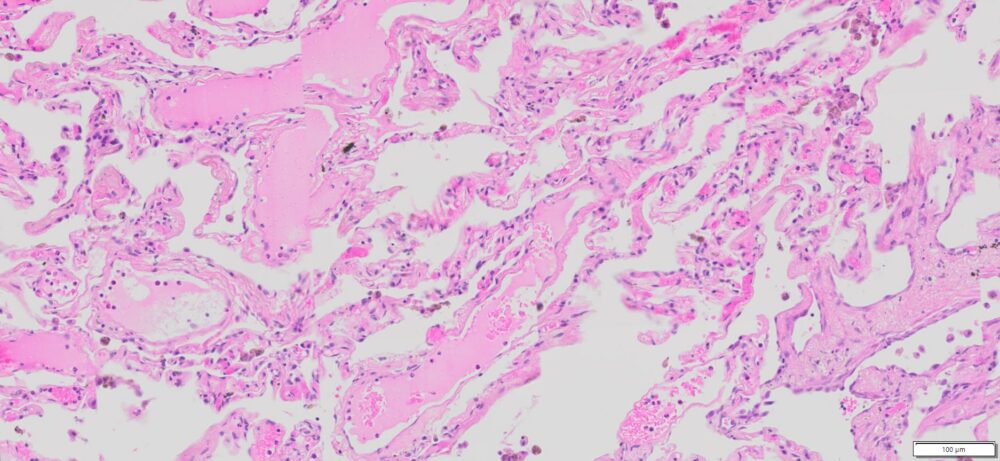

Description

| SKU# | Organ | Pathology Diagnosis | Gender | Age | Grade | TMN | Thickness | IHC Data |

| HuPS-03003A | Human Lung | Lung cancer adjacent normal tissue | Male | 51 | — | — | 5 μm |

Human tissue was fixed in formalin immediately after excision and embedded in paraffin. The tissue sections were 5 µm in thickness and mounted each on positively charged glass slides.